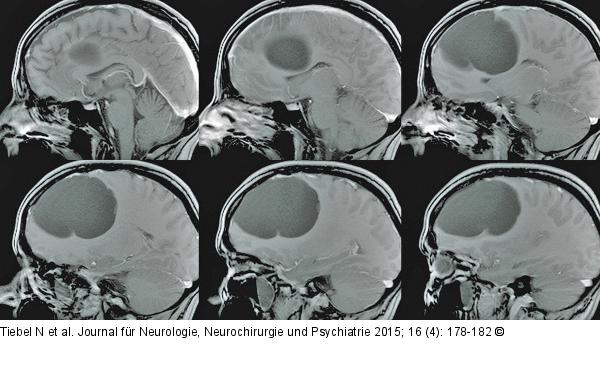

Abbildung 1: Endodermale Zyste Schädel-MRT, T1, sagittal: Präoperativer Befund der endodermalen Zyste mit deutlicher Größenprogredienz im Vergleich zu zystischer Struktur im MRT aus 1999. |

Schädel-MRT, T1, sagittal: Präoperativer Befund der endodermalen Zyste mit deutlicher Größenprogredienz im Vergleich zu zystischer Struktur im MRT aus 1999. |